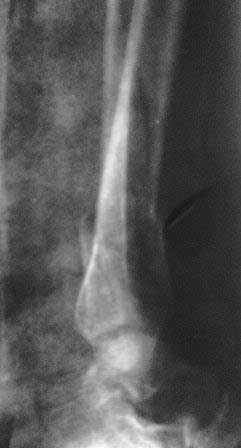

Вялоконсолидирующийся перелом дистального метадиафиза костей левой голени

Пациентка 32 года, травму получила в результате ДТП, лечилась в гор.б-це №? Москвы с 19.07.по04.08.11г скелетным вытяжением, после наложена гипсовая повязка,(р-снимок 1,2.)

после спадения отека гипс переведена в циркулярную, (видимо на другой вид лечения не хватило средств), гипс снят 19.11.11г(снимок-3)

.Жалобы на боли при ходьбе через несколько шагов, увеличение отека в голени и г/стопном суставе, боли ноющего и неприятного характера, хромота, при осмотре отечность голени в с-н/з и г/с суставе, при пальпации умеренная болезненность в н/з голени, подошвенное сгибание в г/с суставе ограничена и болезненна. Работа связана с ходьбой, просить помочь чтобы не потерять работу. Пока в голове только КДО аппаратом Илизарова, уважаемые коллеги помогите советом! Доступно БИОС, пластины DCP. и прилагается последние р-снимки.